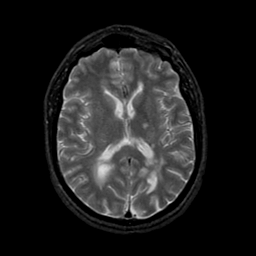

MR Study #21, November 3, 1991 -- Slice #28